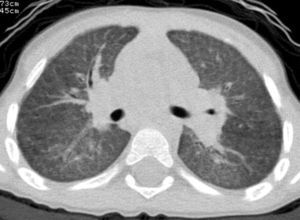

After discontinuation of treatment, the twins did not present any notable episodes of lung infection and enjoyed normal growth. The physical examination was normal, as was the saturometry. At the age of 9, HRCT was repeated in the twin who had the more severe clinical history, observing a reduction in the interstitial lung disease (Fig. 4). Spirometry was performed in both the brothers, giving age-appropriate results.